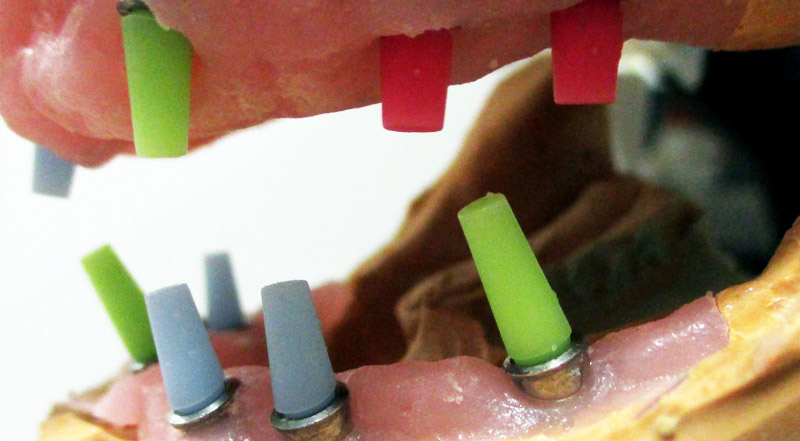

Treballem amb Cad Cam per aconseguir els millors ajustos i una passivitat excel·lent, ajustant-nos a les emergències i perfils dels implants segons petició del Clínic.

Els materials amb els que treballem son de la mateixa casa comercial, així com mecanitzats i els cargols.